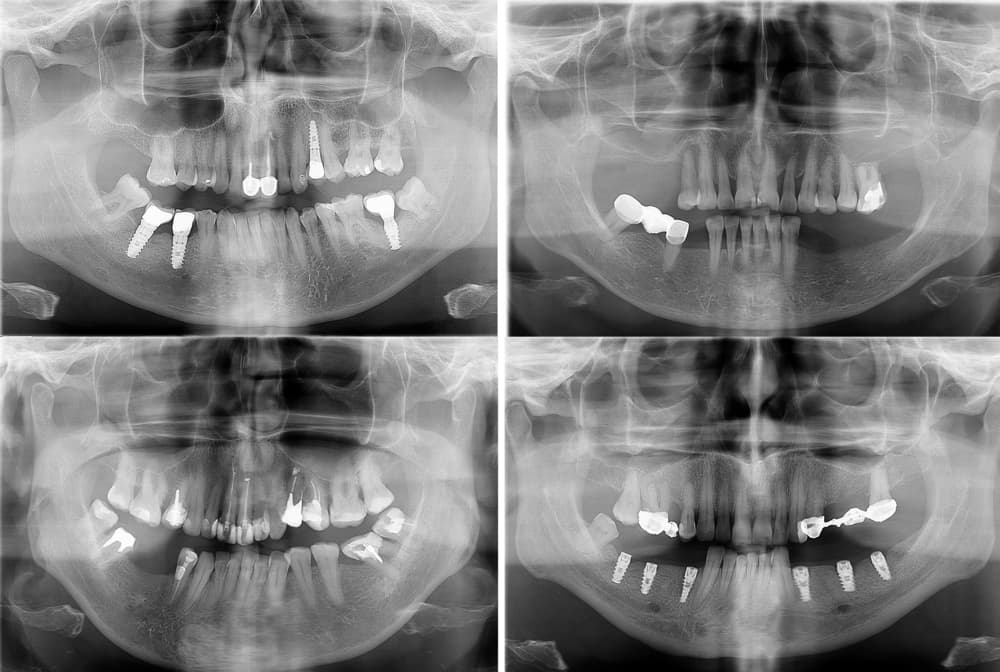

Dental implants are small titanium or zirconia posts surgically placed into the jawbone to act as artificial roots. Over several weeks, the implant undergoes osseointegration, where living bone cells attach firmly to the implant surface. Once healed, the implant can support a crown, bridge, or denture with remarkable stability.

Because implants directly stimulate the alveolar bone, they prevent the resorption process and preserve facial contours. Implants are also bioinert, meaning the body does not reject them, and modern surface treatments (such as sandblasting and acid-etching) enhance bone bonding for long-term success.

When a tooth is lost, this stimulation stops, and the bone begins to resorb (shrink). This can alter facial shape over time, making the cheeks look hollow or the jawline less defined. Dentures and bridges replace the visible part of the tooth but do not address this hidden issue. Dental implants, however, are titanium posts that fuse directly with bone through a process called osseointegration, restoring both form and function.